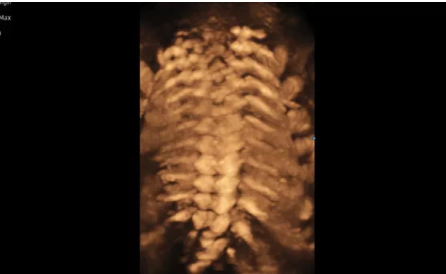

3D/4D成像方面,Hera i 10通過(guò)結(jié)合先進(jìn)的圖像渲染技術(shù),著重加強(qiáng)了邊緣和小結(jié)構(gòu)的可視化能力。